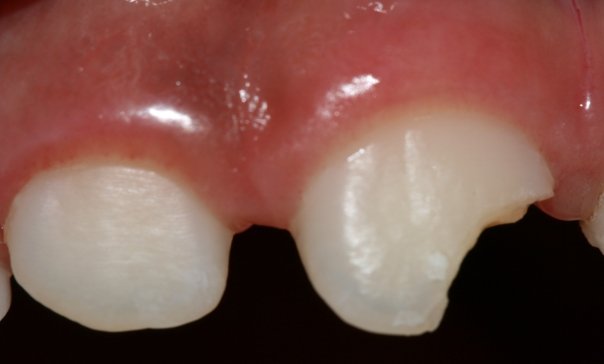

Con los niños siempre hay accidentes y lastimosamente las fracturas en los dientes anteriores son de las más comunes en la práctica dental. En este caso se decidio hacerle unas incrustaciones tipo carilla o mitad corona y con una base de Ionómero de vidrio. Se utilizó ceromero que es un tipo de resina con el que se hacen rellenos blancos.... Sigueme en el blog! gracias.